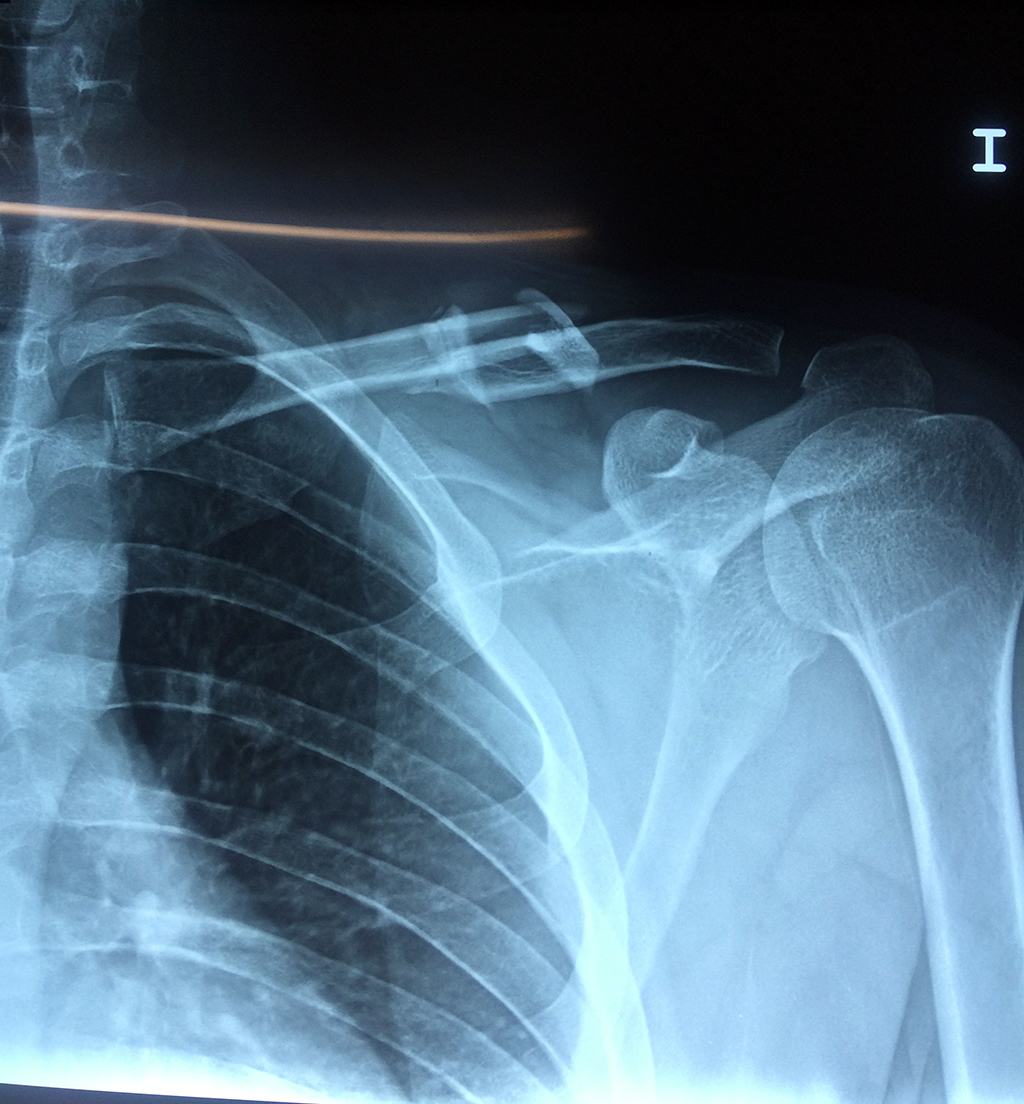

Cirugias en El Salvador - Clavícula